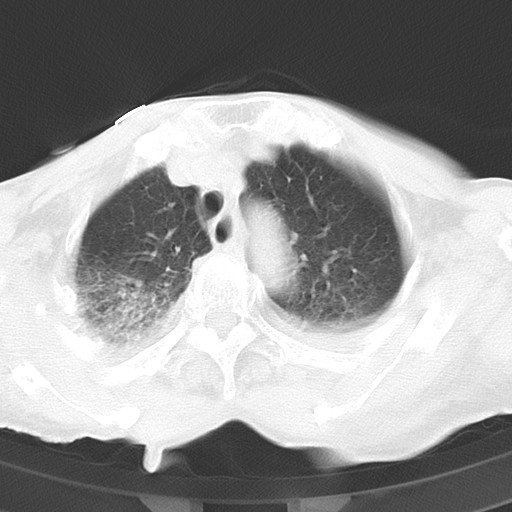

标题: CT21467:女,93岁,摔伤后检查。

女,93岁,摔伤后检查。

考虑感染性病变,建议抗炎治疗后复查。双侧胸腔积液。

右肺炎症,心功能不全伴双侧胸腔积液,右下肺膨胀不全,食管裂孔疝,冠脉钙化,心包少量积液,左侧肋骨骨折,请上传骨窗.

双肺感染合并双侧胸腔积液、胸膜增厚粘连,骨性胸廓未见明确骨折征。